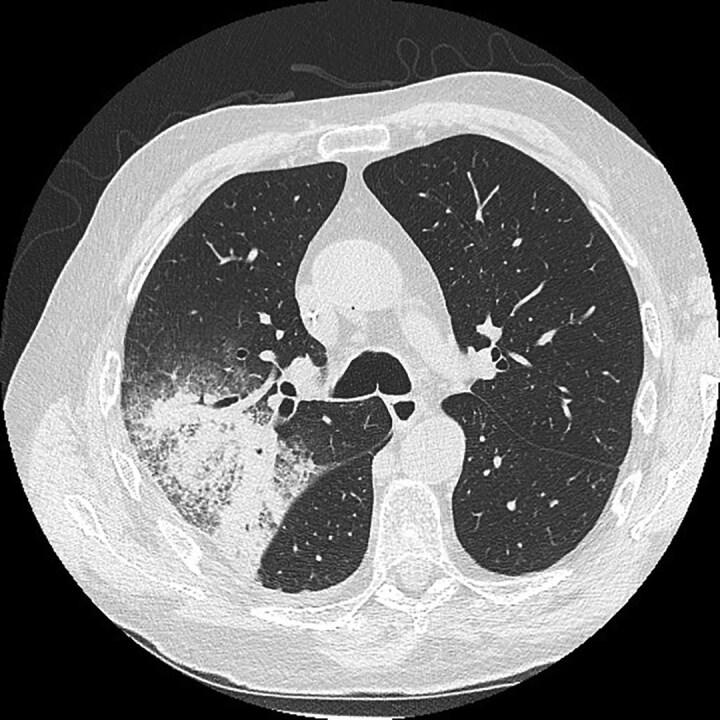

Invasive fungal infection (IFI) due to moulds other than Aspergillus are a significant cause of morbidity and mortality. Non-Aspergillus mould (NAM) infections appear to be on the increase due to an ever-expanding population of immunocompromised hosts. In this review, Mucorales, Scedosporium species, Lomentospora prolificans and Fusarium species are examined in detail, and the microbiology, risk factors, diagnosis and treatment of emerging NAMs such as Paecilomyces variotti, Purpureocillium lilacinum and Rasamsonia are summarized. The challenges in diagnosis are emphasized and the emerging importance of molecular methods is discussed. Treatment of IFI due to NAMs is a multi-pronged and multi-disciplinary approach. Surgery, correction of underlying risk factors, and augmentation of the host immune response are as important as antifungal therapy. Many of these NAMs are intrinsically resistant to the currently licensed antifungal agents, so selection of therapy needs to be guided by susceptibility testing. There are new antifungal agents in development, and these have the potential to improve the efficacy and safety of antifungal treatment in the future. Ongoing research is required to fully delineate the epidemiology of NAM infections, and to develop better diagnostic tools and treatments so that outcomes from these infections can continue to improve.

由曲霉菌以外的霉菌引起的侵袭性真菌感染(IFI)是发病和死亡的重要原因。由于免疫功能低下宿主群体不断扩大,非曲霉菌霉菌(NAM)感染似乎呈上升趋势。在本综述中,对毛霉目、帚霉属、多育镰刀菌和镰刀菌属进行了详细研究,并总结了诸如拟青霉、淡紫紫孢菌和拉氏菌等新兴NAM的微生物学、危险因素、诊断和治疗方法。强调了诊断方面的挑战,并讨论了分子方法日益重要的作用。治疗由NAM引起的IFI需要采取多方面、多学科的方法。手术、纠正潜在危险因素以及增强宿主免疫反应与抗真菌治疗同样重要。这些NAM中的许多对目前已获许可的抗真菌药物具有内在抗性,因此治疗选择需要以药敏试验为指导。目前正在研发新的抗真菌药物,这些药物有可能在未来提高抗真菌治疗的疗效和安全性。需要持续开展研究,以全面描述NAM感染的流行病学情况,并开发更好的诊断工具和治疗方法,从而使这些感染的治疗效果不断改善。